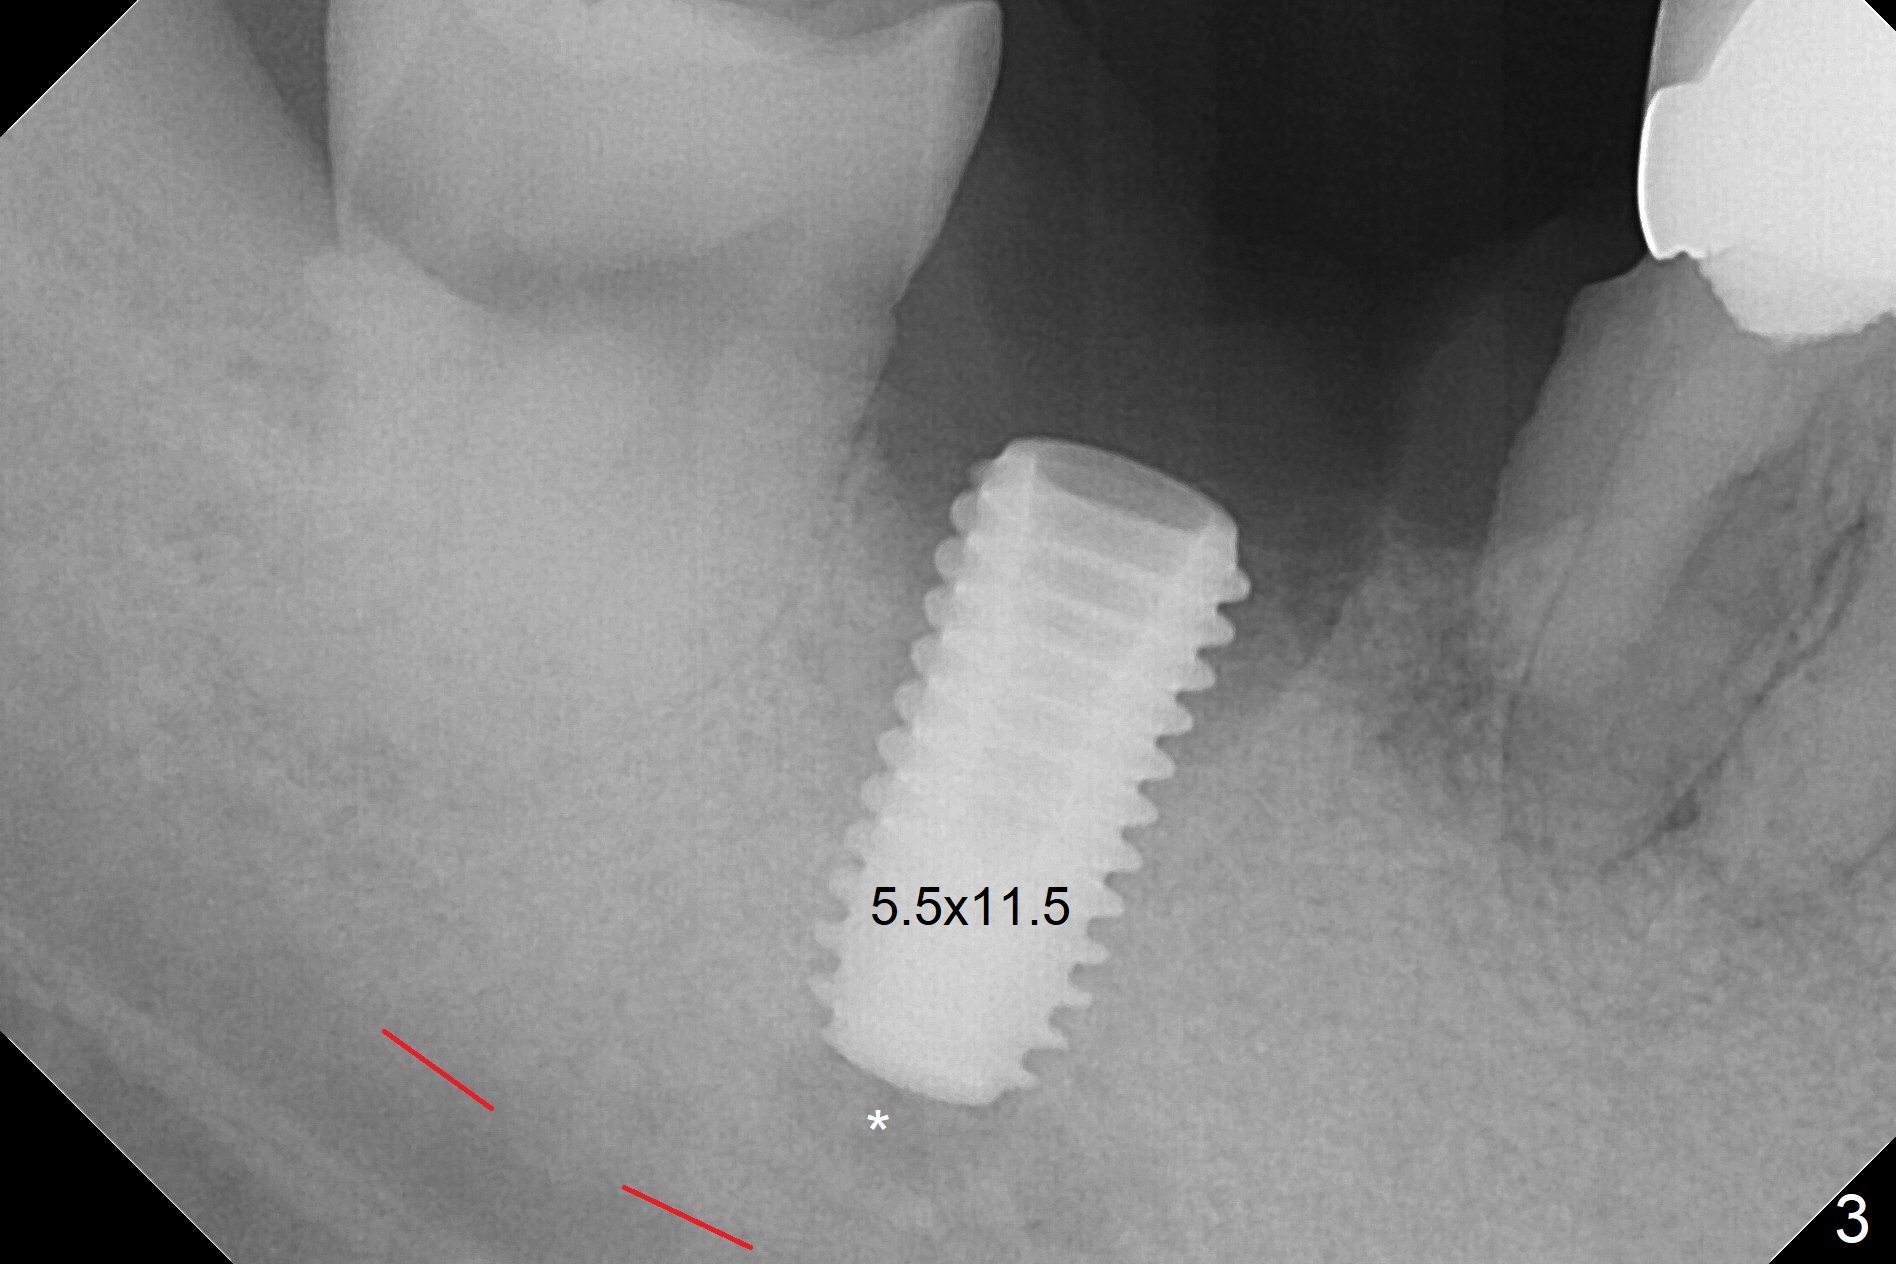

Although the tooth #30 has distobuccal root exposure (Fig.1 <), it is asymptomatic.  In contrast the tooth #31 with the distoocclusal caries (*) is symptomatic.  After use of 2 mm drill for 18 mm (lingual gingival margin), a calculated parallel pin is inserted (Fig.2 (D: 2 distal roots of the tooth #30)).  It appears that a 11.5 mm long implant is appropriate for the site; a 5 mm cuff is expected.  Following 4.8 mm drill, a 5.5x11.5 mm implant is placed initially (Fig.3) with an apical space (*) and clearance from the Inferior Alveolar Canal (red dashed line).  The implant is placed deeper with placement of a 6.5x4(5) mm abutment and bone graft (*, Fig.4,5).  After placement of collagen membrane over the graft, an immediate provisional is fabricated (Fig.6 P) with clearance from the opposing tooth (Fig.7 *).  There is no bone loss 3.5 months postop (Fig.8).  In fact the abutment has not been seated completely since its placement (Fig.4,5,8).  The crown/abutment dislodges 3 years 3 months post cementation (Fig.9).  The latter occurs for long incubation time because of opposing partial denture (Fig.10).  After trimming proximal surfaces (Fig.11: arrowheads), the abutment remains incompletely seated (Fig.11) due to possible crestal bone interference (Fig.11 *).  The smaller abutment by itself remains unseated (Fgi.12).  One size small one is completely seated (Fig.13).  Impression is taken.  Two weeks later the abutment margin is supragingival.  After screw torque at 20 Ncm, the crown is cemented with access hole.  Excess cement is removed.